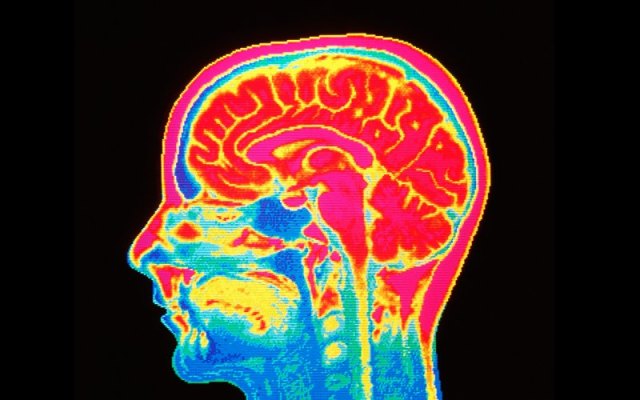

A pioneering study conducted by leading researchers at the University of Sheffield has revealed blood types play a role in the development of the nervous system and may impact the risk of developing cognitive decline.

The research, carried out in collaboration with the IRCCS San Camillo Hospital Foundation in Venice, shows that people with an ‘O’ blood type have more grey matter in their brain, which helps to protect against diseases such as Alzheimer’s, than those with ‘A’, ‘B’ or ‘AB’ blood types.

Research fellow Matteo De Marco and Professor Annalena Venneri, from the University’s Department of Neuroscience, made the discovery after analysing the results of 189 Magnetic Resonance Imaging (MRI) scans from healthy volunteers.

The researchers calculated the volumes of grey matter within the brain and explored the differences between different blood types.

The results, published in the Brain Research Bulletin, show that individuals with an ‘O’ blood type have more grey matter in the posterior proportion of the cerebellum.

In comparison, those with ‘A’, ‘B’ or ‘AB’ blood types had smaller grey matter volumes in temporal and limbic regions of the brain, including the left hippocampus, which is one of the earliest part of the brain damaged by Alzheimer’s disease.